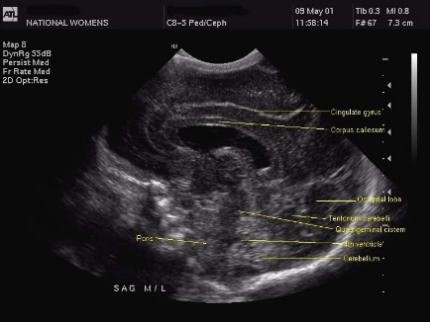

1. Midline Sagittal

The image gives some important information. It shows the cerebellar vermis as a bright image with the 4th ventricle right in front of it. Right below the cerebellar vermis is the cisterna magna, which is not that bright. With the cingulated gyrus right above, the corpus callosum sweeps from anterior to posterior. A bit further above the posterior fossa is the parieto-occipita sulcus.